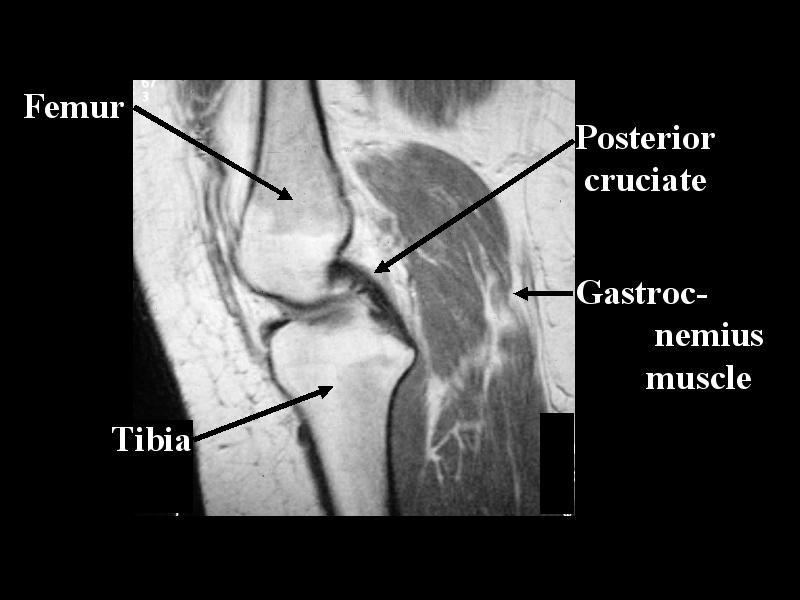

MS 200 MR KNEE 67